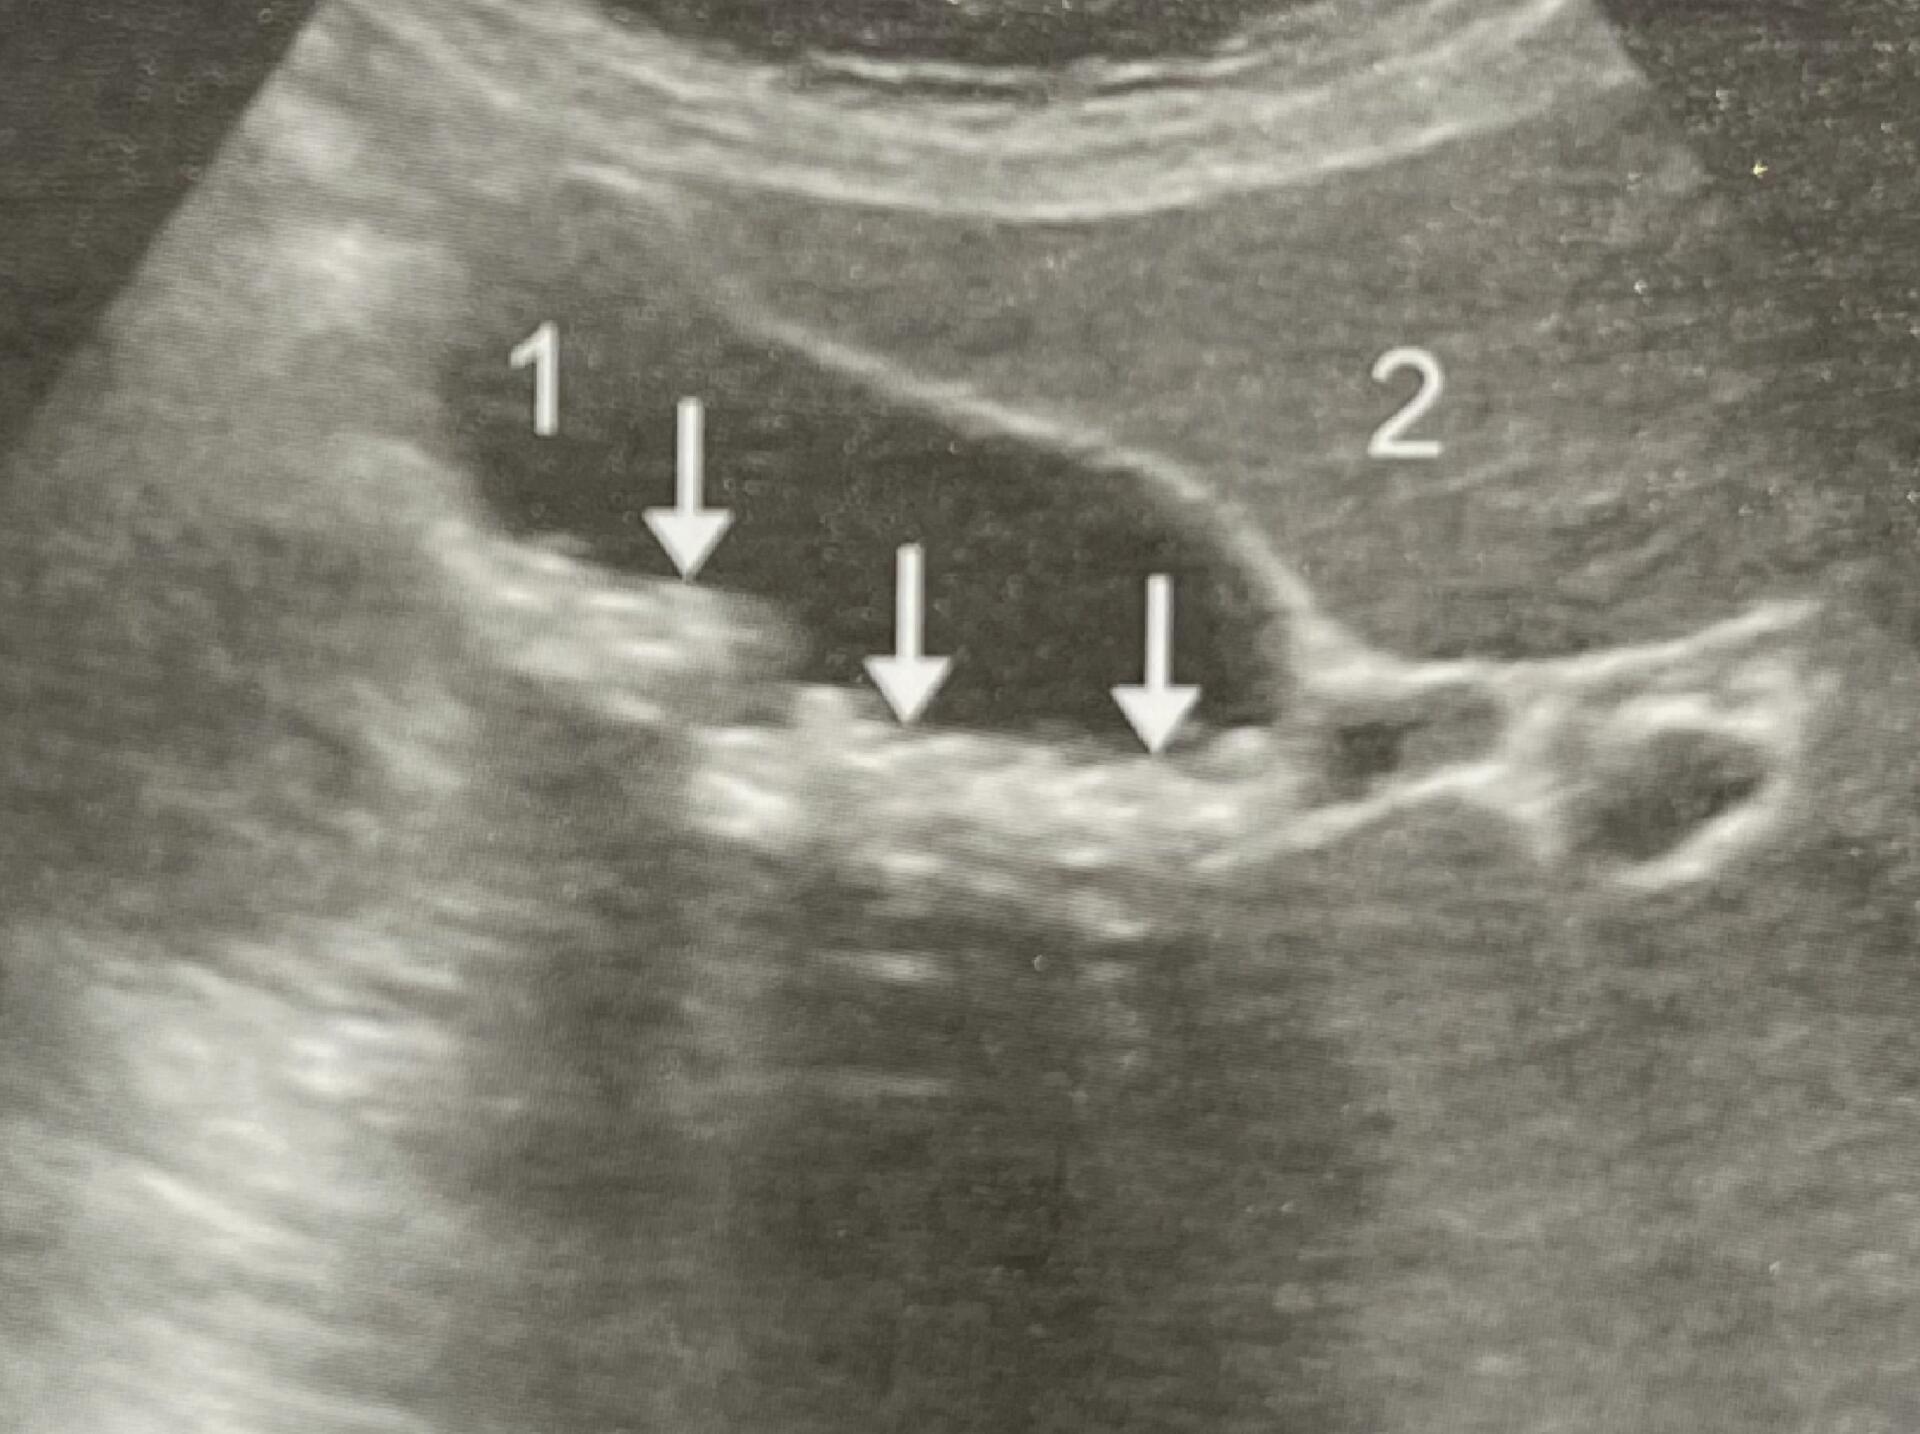

b超下泥沙样胆囊结石影像

图片尺寸1920x1434